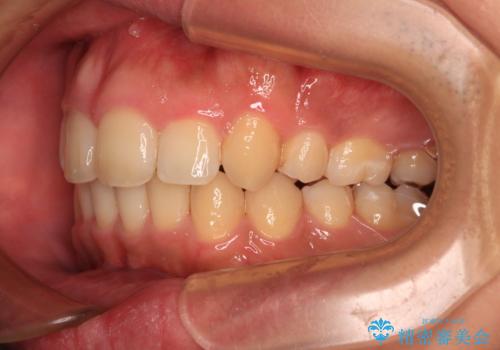

- 1年2ヶ月

上顎歯列全体がスムーズに後方移動でき、1年で治療を終えることができました。